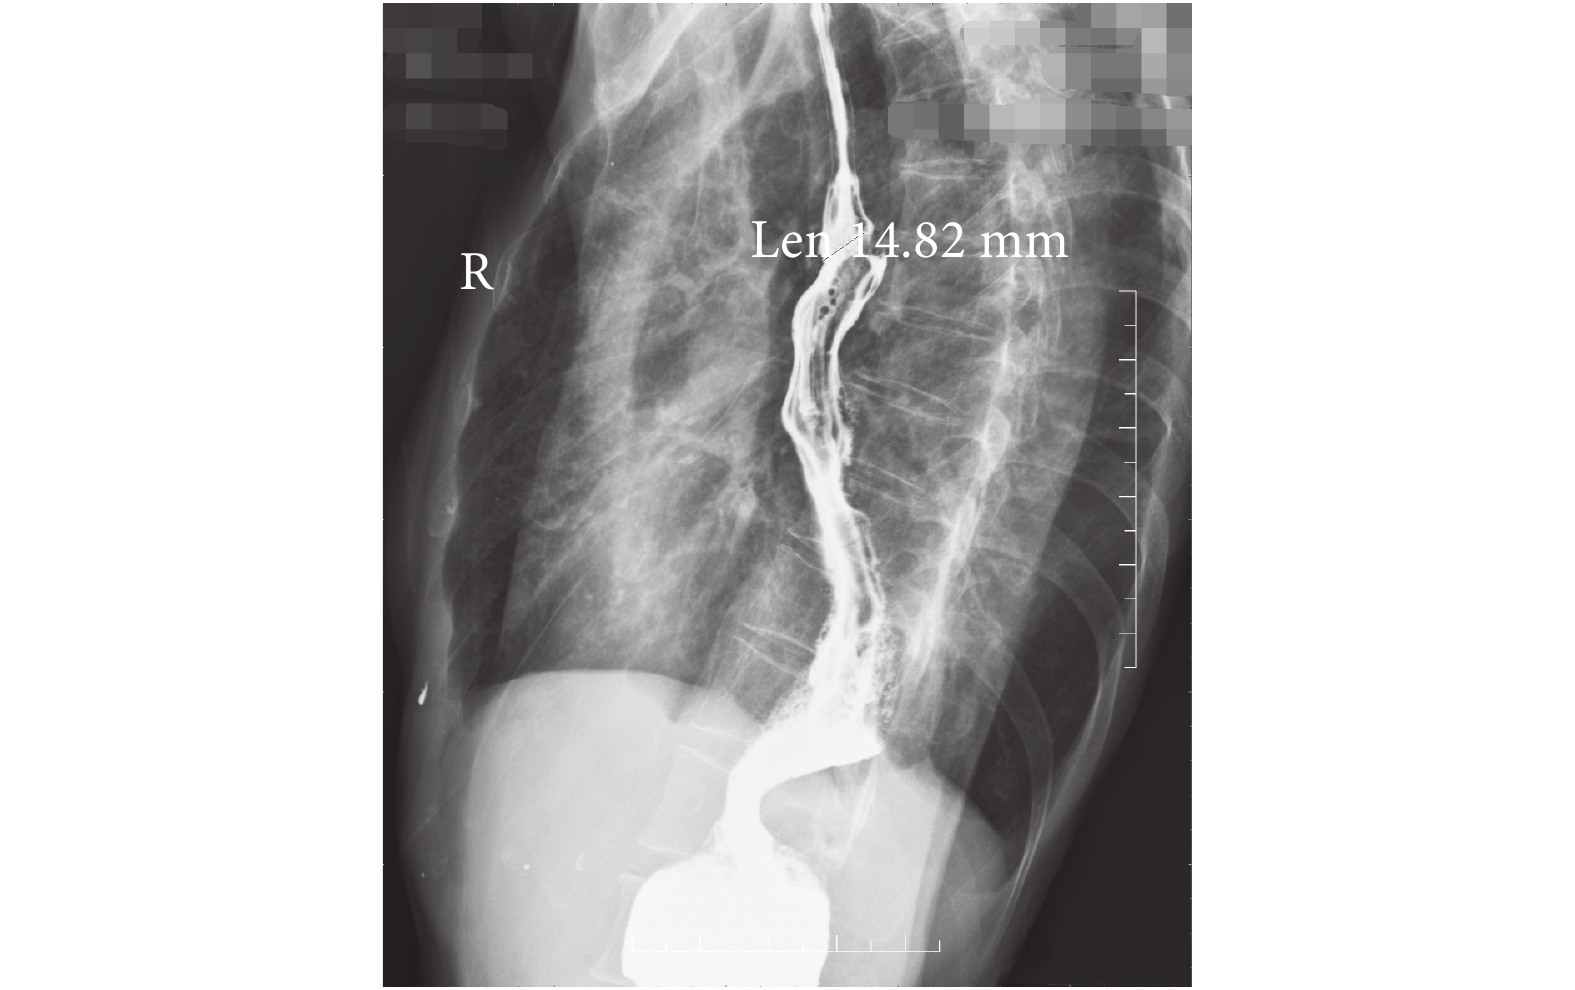

試驗組和對照組各有 2 例術后發生吻合口瘺,均經保守治療治愈。除發生吻合口瘺外所有患者術后 3~6 d 停胃腸減壓,術后 5 d 試飲水,進流質飲食 5 d 后改半流質飲食,繼而軟食,少量多餐,12~14 d 左右出院,出院一周進普通食物。術后病理示 116 例食管鱗癌,14 例腺癌,上、下切緣無癌殘留。結果表明,對照組胸腔引流管留置時間為(5.8±6.8)d,試驗組(5.9±6.7)d,差異無統計學意義。對照組腸蠕動恢復時間為(2.6±0.7)d,試驗組(2.6±0.8)d;對照組吻合口門齒距為(21.8±5.0)cm,試驗組(20.3±4.2)cm,差異均無統計學意義。對照組術后 6 個月吻合口狹窄程度輕度 7 例,中度 10 例,重度 3 例(其中 2 例吻合口瘺患者 1 例為中度狹窄,1 例為輕度狹窄);試驗組分別為 5 例、2 例和 1 例(其中 2 例吻合口瘺患者均為輕度狹窄),差異有統計學意義(表 2)。術后 6 個月食管鋇餐造影結果提示:試驗組吻合口左右直徑為(15.0±3.1)mm,對照組(13.2±3.9)mm,試驗組吻合口前后徑(13.1±3.0)mm,對照組(11.5±3.8)mm,差異均有統計學意義。造影所測吻合口直徑見圖 2、圖 3。

事實上,影響術后吻合口大小的不只是直徑,還包括吻合口面積,吻合口局部食管肌肉的順應性等。本研究的結果顯示通過食管胃斜行吻合,可以減少吻合口狹窄的發生率。可能機制為斜行吻合使食管的縱行肌纖維不在一個水平平面上切割,因此,術后吻合口疤痕形成時,相鄰的肌纖維間固定不像水平吻合時那么堅固,通過進食時的食物擴張作用,可以降低疤痕攣縮的程度,從而減輕吻合口狹窄。基于斜行吻合同時減輕了前后徑和左右徑的疤痕攣縮,因此,在吻合口面積的擴大上應有差別,從而對患者進食情況產生積極影響。從狹窄評價指標看,食管吞鋇造影能較好地反映食管擴張功能,在吞鋇片上采用測量吻合口左右徑和前后徑可以較好地了解患者進食時食管擴張的程度。結合吞咽困難 Stooler 分級法,可從主觀和客觀兩方面更好地評價 45 度吻合的手術效果。但隨著手術技術的發展,尋找更客觀、更有意義的吻合口狹窄評價指標仍是食管外科研究的方向和目標。